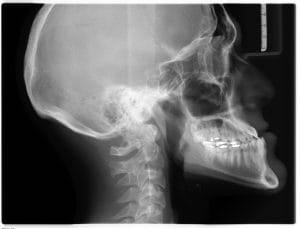

Mange blir overrasket over at slike plager kan henge sammen med kjeveleddet (TMJ). Kjeven samarbeider med og påvirker omkringliggende muskulatur og ledd, og kan da skape en rekke plager som ikke bare påvirker kjeveleddet. I denne artikkelen skal vi gå gjennom hvilke plager som kan oppstå, og hvordan behandling kan hjelpe.

Terapeuten undersøker både kjeve, nakke og hals for en helhetlig vurdering av kjeveleddene. Her testes både leddutslag, muskelkraft, palpasjon og om det er mulig å reprodusere smerten på noe vis. Andre faktorer som ikke er strukturelle vil også vurderes for å finne ut hvorfor smertene har oppstått. Undersøkelsen som gjennomføres kan inneholde: